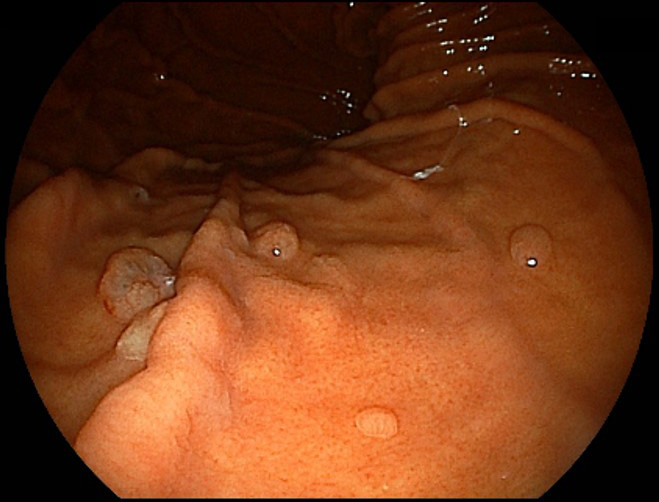

胃ポリープ

粘膜のできもので、多くは隆起性です。ほとんどは、胃底腺ポリープと過形成ポリープです。胃底腺ポリープはピロリ菌感染がない場合にできやすく、胃がんに進行することはほとんどありません。過形成ポリープは、ピロリ菌感染があると生じやすく、内視鏡で観察すると表面が赤く、デコボコしていることもあります。大きくなると出血や貧血を起こすことがあり、がんを合併する可能性があります。ピロリ菌の除菌治療でポリープが縮小することがあるため、それによって内視鏡による切除が可能になるケースもあります。